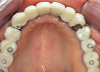

Fig 20. Frontal view at 20-year follow-up.

Figure 20

In 2020, the patient presented to the NYUCD Periodontology and Implant Dentistry Clinic. A clinical examination and radiographic evaluation showed that the patient's maxillary arch still exhibited good peri-implant soft-tissue health and stable marginal bone level with slight bone loss on implants Nos. 2, 6, 8, and 11 (Figure 18 through Figure 20). The maxillary prosthesis showed adequate stability with a slight chipped suprastructure on the porcelain on the right side. The patient was advised to substitute the implant-supported, screw-retained hybrid acrylic complete denture in the maxilla with a fixed, implant-supported, screw-retained prosthesis, which she declined due to financial considerations.